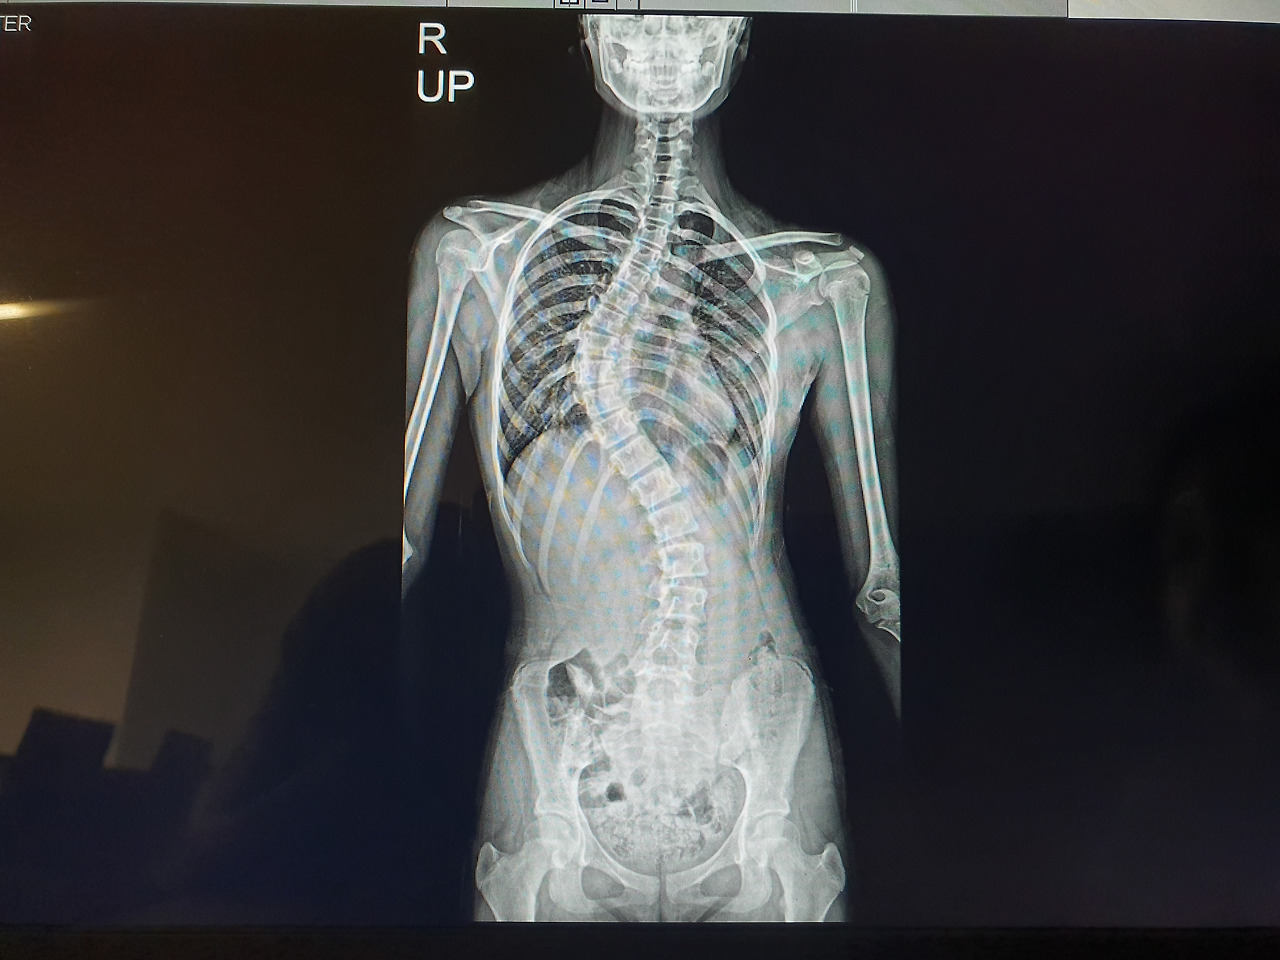

차례가 되어 떨리는 맘으로 진료실에 들어갔다. 교수님은 인사도 받는둥 마는둥 하시고 엑스레이만 보시더니,

지금 초가집 지붕에 불났어요 불나서 활활 타고 있는데 뭘 꾸물거려요?

아직 성장판도 안닫혔고...순식간에 더 휘어요 수술해요 일정 잡아서.

이건 아직 정확하게 밝혀진 이유는 없다고 한다. (그래서 특발성 척추측만증이라고 진단한다) 다만 이유도 없고 선천적으로 타고났을 거라 추측하며, 급성장기때 척추가 급격하게 휜다고 했다. 아이는 만 11세, 초등 5학년이었고, 이미 키가 많이 자라고 있을 때였다. 아마 어릴적에도 조금 휜게 보였을 텐데 역시나 무심한 애미는 전혀 몰랐다. 물론 한쪽 날개뼈가 조금 튀어나와 있다는 건 알고 있었지만 뭐 완벽한 대칭일 수는 없기에 별 대수롭지 않게 생각했다.

안타깝게도 수술 외에는 방법이 없다. 경미한 각도야 운동이나 근육 증강 등으로 통증을 완화할 수는 있어도 우리 아이처럼 심각하게 척추가 휘는 경우에는 교정도 되지 않고 교정기도 착용해도 별 의미가 없다. 게다가 아직 성장판이 닫히지 않아서 갈수록 더 휠거라고 했다. 성장이 멈추면 척추가 휘는 것도 멈춘다. 하루가 다르게 키가 쑥쑥 큰다고 좋아했었는데 마냥 좋아할 일도 아니었던 거다.

척추가 이렇게 휠 수도 있다니요...